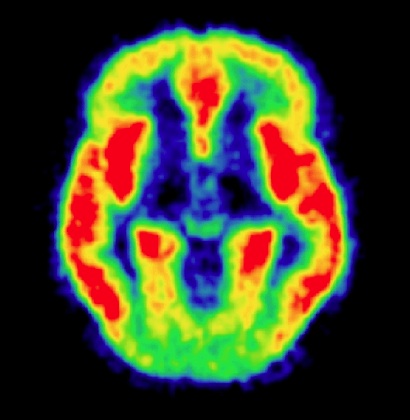

![]() | Pathophysiology and Treatment of Bipolar Disorder as Assessed by in vivo Imaging | ||

| Volunteers needed | Eligibility | ||

| Volunteers with bipolar disorder Learn more | Adults 18 - 65 who have bipolar disorder and are currently depressed | ||

| Healthy adults Learn more | Healthy adults 18 - 65 with no history of psychiatric disorders | ||